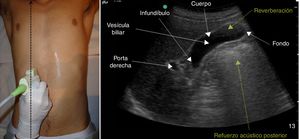

La vía biliar (colédoco) se localiza en un corte oblicuo, paralela y por delante de la porta, junto a la arteria hepática (presentan grosores similares y el Doppler puede ayudar a diferenciarlas). Si se gira el transductor 90° se visualizarán estas estructuras transversalmente (imagen del «ratón Mickey») (fig. 6). El calibre del colédoco debe ser < 6mm, excepto en pacientes colecistectomizados (< 10mm). Los conductos biliares intrahepáticos no se ven en condiciones normales. La vesícula biliar tiene forma ovalada (aunque variable20), sin ecos en su interior, < 4-5cm de diámetro transversal (el más fiable) y < 10cm de diámetro longitudinal. La posición del fondo es variable, por lo que se deben hacer diferentes cortes oblicuos hasta conseguir un corte longitudinal de la vesícula.

Escenarios clínicos en atención primaria y evidenciaLas situaciones clínicas en las que una ecografía de vías biliares puede ser útil para ayudar al diagnóstico y disminuir la incertidumbre en la consulta de AP o en urgencias extrahospitalarias son múltiples21, aunque podemos señalar como más frecuentes (tabla 2) el dolor en el hipocondrio derecho, con o sin fiebre (a veces el dolor es más difuso o difícil de localizar), las alteraciones analíticas tipo colostasis (elevación de fosfatasa alcalina, gama glutamil transpeptidasa, bilirrubina), el síndrome constitucional y la ictericia clínica. También es útil para el seguimiento de lesiones como los pólipos de vesícula biliar22, que generalmente son hallazgos incidentales. Las imágenes ecográficas patológicas más frecuentes en cada una de estas situaciones clínicas, y que el MF que realiza ecografía clínica debe saber reconocer, son: la colelitiasis23, estructuras hiperecogénicas en el interior de la vesícula con sombra acústica posterior (fig. 7); la colecistitis24, cuyos signos, aunque no específicos, son el aumento de grosor de la pared vesicular, líquido perivesicular, presencia de litiasis o barro biliar (fig. 8); la dilatación de la vía biliar25,26 obstructiva, y los tumores de vesícula y vía biliar27.